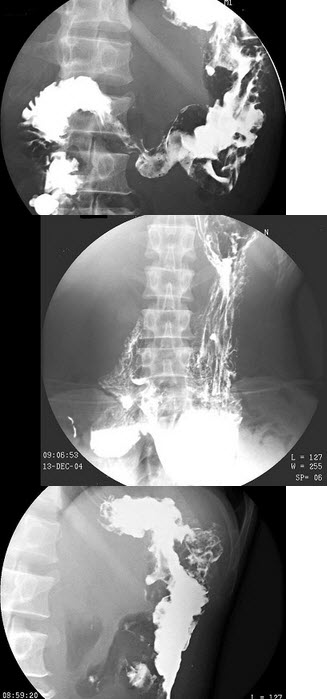

A.肝

男,63岁,进行性吞咽困难1月。食管钡餐示:食管下段粘膜不规则充盈缺损,管腔狭窄,贲门扩张欠佳。

病变侵及食管的()